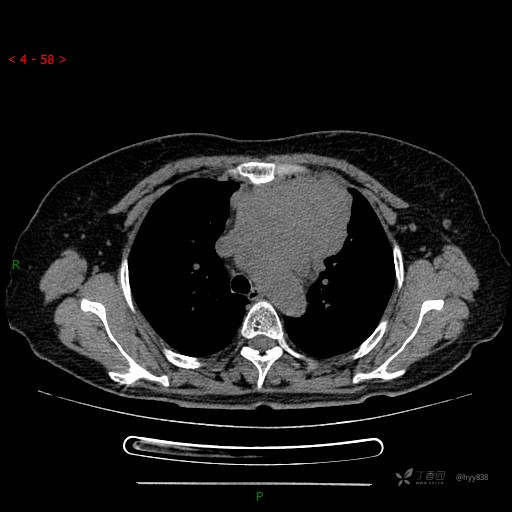

简要病史:患者诉3月余前患新冠肺炎,出现持续性胸闷,活动后可缓解,无胸前区压榨感,无畏寒发热不适,无胸痛咯血、呼吸困难,无恶心、呕吐,无腹痛、腹胀、腹泻等不适,未予以重视,未行特殊处理。患者胸闷持续存在,为进一步诊治,3天前于本院查胸部CT提示前纵膈团块状软组织密度影,肿瘤性病变可能,心包积液,左上肺磨玻璃结节,右下肺增殖灶可能建议进一步检查。门诊以“前纵膈占位” 收入我科。 患者本次起病来精神、食欲、睡眠尚可,大小便正常,体力、体重无明显变化。

辅助检查:CT

临床诊断:纵隔占位

静脉期